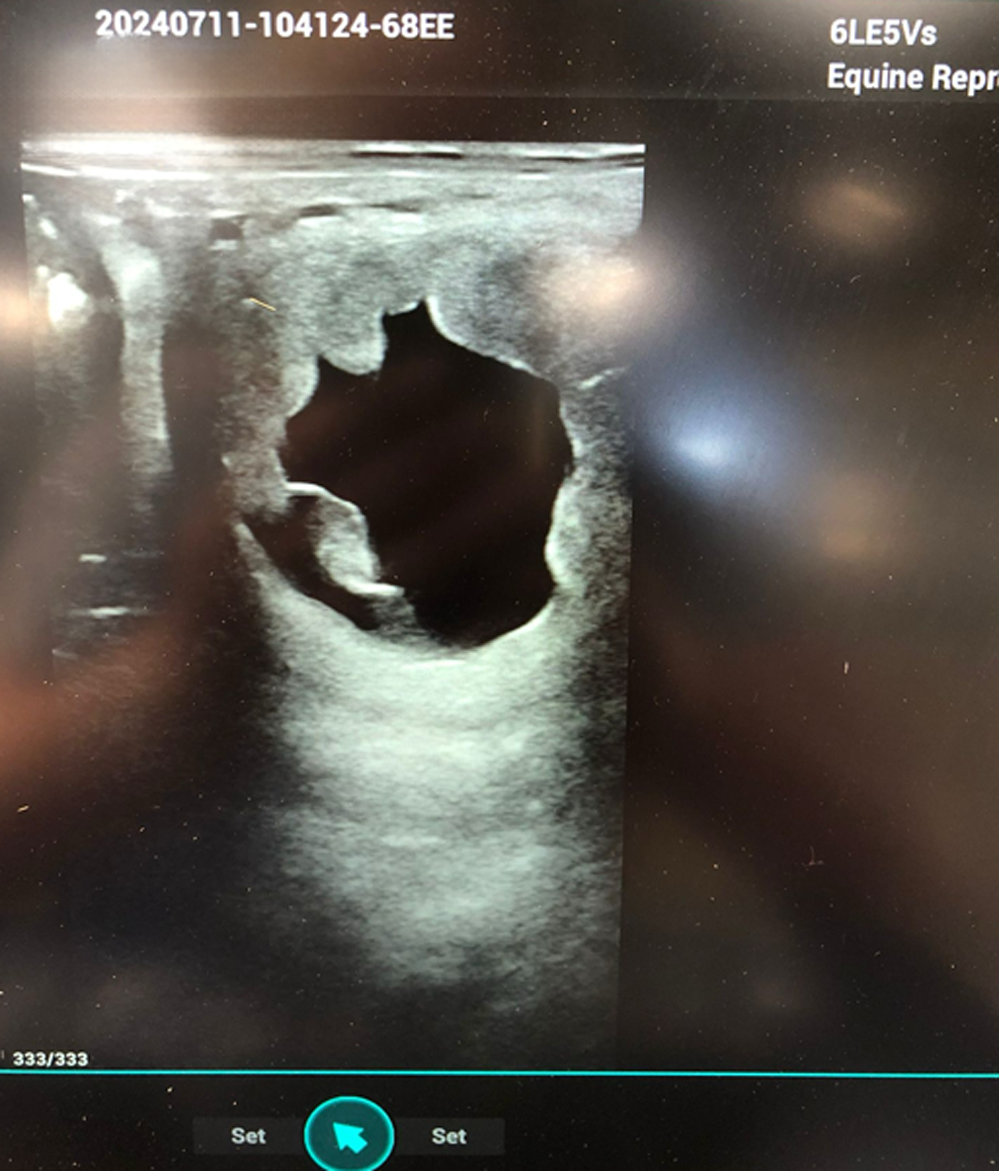

Overzicht van onze diensten

Als dierenartsen met een passie en specialisatie in paarden, staan wij klaar om zowel recreatie- als sportpaarden de beste zorg te bieden. Wij combineren jarenlange ervaring met up-to-date kennis en moderne technieken, zodat uw paard steeds in de beste handen is.